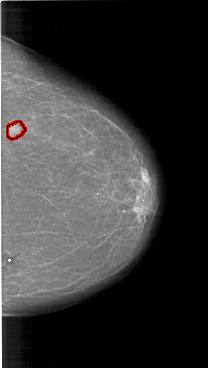

FILE: A_1150_1.RIGHT_MLO.OVERLAY

TOTAL_ABNORMALITIES 1

ABNORMALITY 1

LESION_TYPE MASS SHAPE IRREGULAR MARGINS ILL_DEFINED

ASSESSMENT 5

SUBTLETY 5

PATHOLOGY MALIGNANT

TOTAL_OUTLINES 1

BOUNDARY